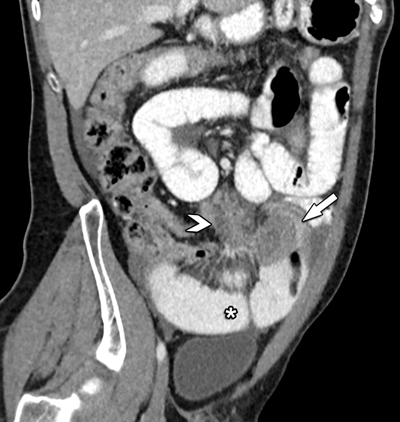

Figure 2

Oblique coronal view of contrast-enhanced CT shows the close relation between the mesenteric mass (arrowhead) and its extension towards the small bowel (arrow). Note the distended small bowel loops (*).